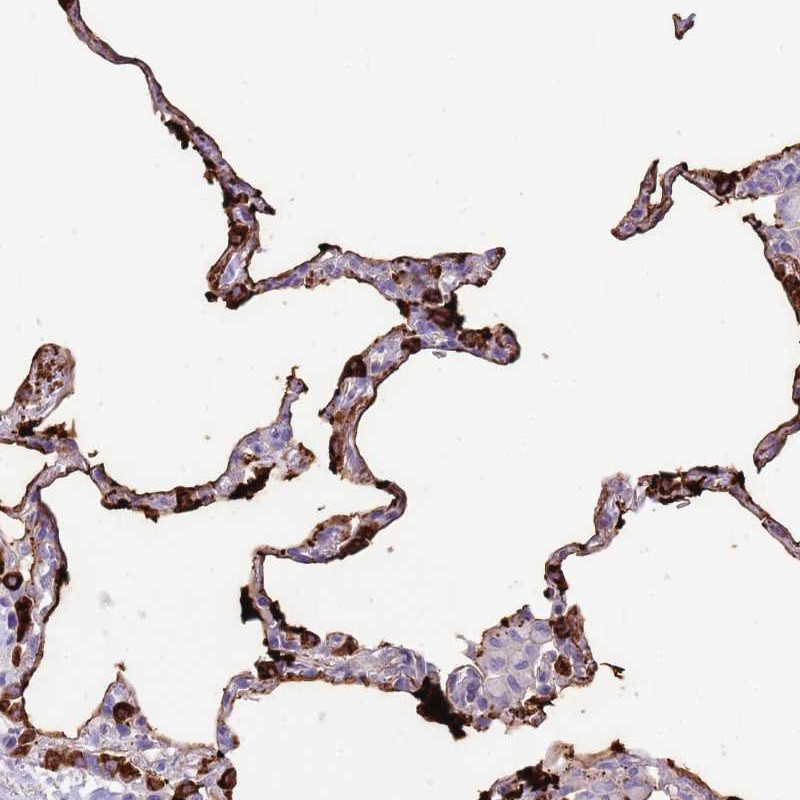

Immunohistochemical staining of human lung shows strong cytoplasmic positivity in a fraction of pneumocytes.